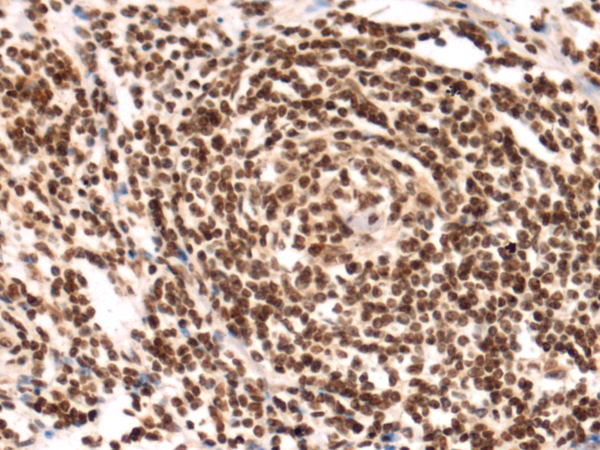

ELISA, IHC |

IHC positive control: |

Human gastric cancer |

IHC Recommend dilution: |

200-300 |